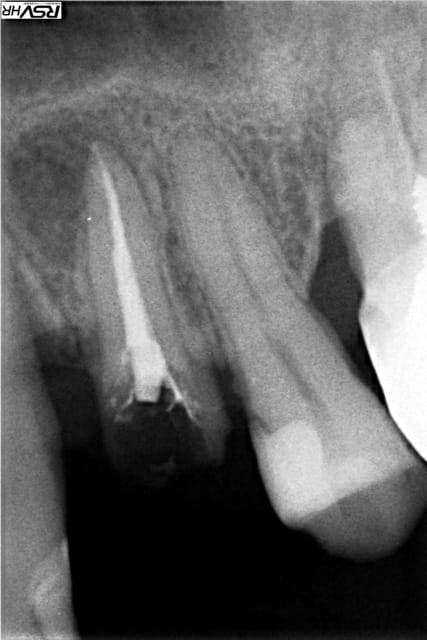

Par exemple vendredi dernier. Je traite donc carie 23 + carie 25 + RTE 24 avec élongation coronaire + couronne provisoire dans la séance (cf. photos jointes.

Je fais donc mes compos en premier, avant que ca saigne de partout :p et en prenant ma radio de contrôle quant au RTE de la 24 je vois du gris entre mes compos et les dents.

Ce n'est probablement pas un décollement, mais une excès d'adhésif non radio opaque entre ta dent et le composite. As tu pris des radios juste après la pose du composite pour comparer ?

J'ai collé deux morceaux de compos avec l'adhésif et on voit le liseré.

A priori c'est l'adhésif que je vois.